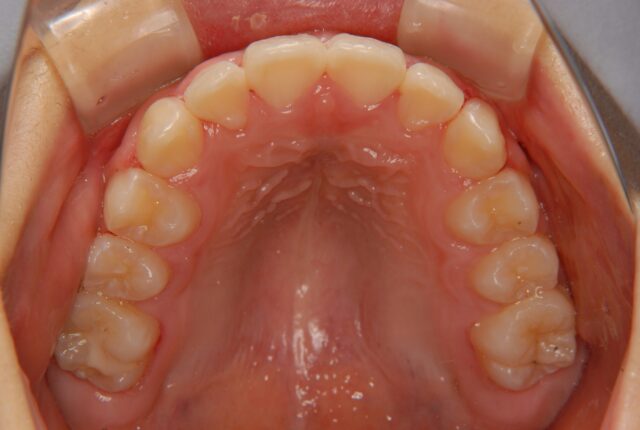

唇側矯正 小児矯正 反対咬合(受け口)の治療例【非抜歯】 この治療例は上下顎歯の唇側より矯正装置を装着して、反対咬合の改善を行った写真です。 治療前 治療後 主訴 受け口を治したい 診断名あるいは主な症状 下顎前突 年齢 10才 治療に用いた主な装置 唇側矯正装置 抜歯部位 非抜歯 治療期間 約2年 通院回数 24回 治療費概算 880,000円(税込) リスクと副作用 反対咬合を改善する時に上下の歯がぶつかり破折する可能性がある。下顎が後方に押し込まれ、顎関節に負担をかける可能性がある。